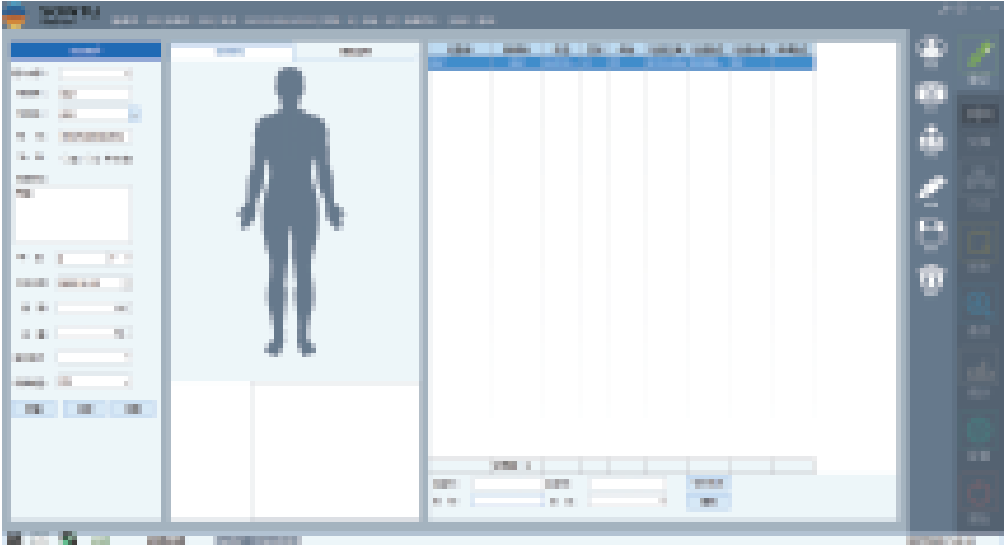

-

登记

-

保存

-

打印

- 04

深图软件操作系统:

一键即可完成辅助诊断,定位可疑病变